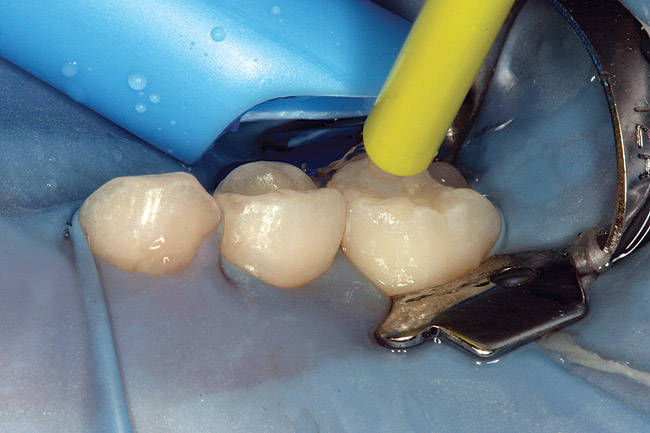

Caries infiltration is a simple, straightforward technique. Before treatment, the tooth should be thoroughly cleaned and isolated with a rubber dam (Figure 5 and Figure 6). Treatment kits contain all of the materials required for the technique (except the rubber dam), including specially designed proximal tips that are used for accurate delivery of the acid etch and infiltrant resin during the procedure. These carriers consist of an ultrathin film perforated on one side for direct placement at the treatment site, which protects adjacent teeth. The tips swivel 360, allowing application from different angles. All syringes contained in the kit are screw-type applicators, which ensure controlled extrusion of the materials.

Specially designed dental wedges are inserted to slightly separate the carious tooth from adjacent teeth. A 15% hydrochloric gel is used to remove the "pseudointact" surface and open the pore system of the incipient lesion body (Figure 7).85 After rinsing (Figure 8), the area is dried with ethanol (Figure 9), followed by dry air. Then, the infiltrant is applied and allowed to penetrate the lesion pores by capillary action for 3 minutes (Figure 10). Any excess material is removed with dental floss, and the infiltrant is light cured from three angles for 40 seconds (Figure 11). A second layer of infiltrant is applied for 1 minute, and light cured for 40 seconds (Figure 12).86 It should be noted that the infiltrant is not radiopaque because fillers would affect the viscosity. Efficacy of the treatment can be tracked at future visits by lack of lesion progression.

Figure 6  Rubber dam and wedge in place.

Figure 6

Figure 7  Matrix in place showing extrusion of hydrochloric acid.

Figure 7